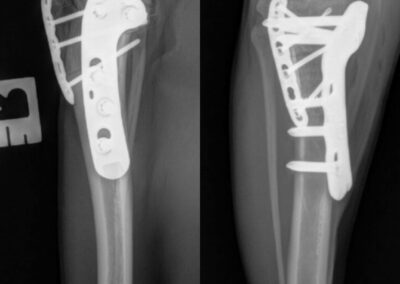

Fracture Repair

We provide surgical fracture repair for many types of broken bones. Treatment plans are individualized based on the location and complexity of the fracture, your pet’s age and size, and overall health.

Radius Fracture After

Large Dog Radius Fracture Before

Large Dog Radius Fracture After #1

Large Dog Radius Fracture After #2